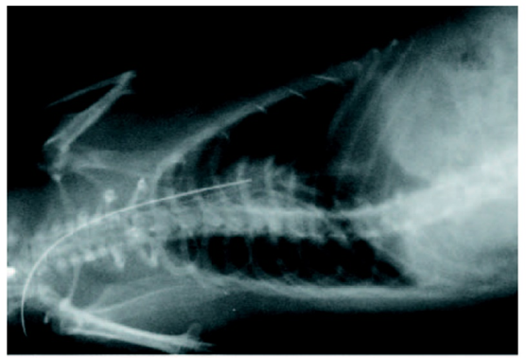

Infective endocarditis (IE) is a prototypical biofilm-associated infectious disease of the cardiovascular system, characterized by a high mortality rate (Fig. 1). Clinical management of IE still relies on prolonged administration of high-dose antibiotics and is often complicated by frequent recurrence. My research has demonstrated that host factors significantly enhance the virulence of IE pathogens. For instance, platelets contribute to biofilm formation and antibiotic resistance in IE pathogens (Fig. 2). Furthermore, aggregates formed between bacteria and platelets stimulate infiltrating neutrophils to release neutrophil extracellular traps (NETs), which in turn activate additional platelets and promote thrombus formation. This cascade contributes to the expansion and maturation of IE vegetations (Fig. 3).